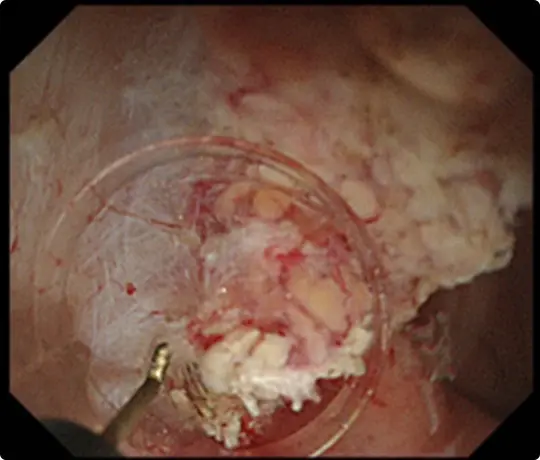

穿孔(壁に穴があくこと)などの問題なく、病変を切除しました。切除後は潰瘍が出来ますが、1~2ヵ月で治ります。

切除した検体をピンで伸ばしています。ホルマリンで固定後、病理診断を行います。病理診断で腫瘍は完全に切除されており、治癒と判定されました。